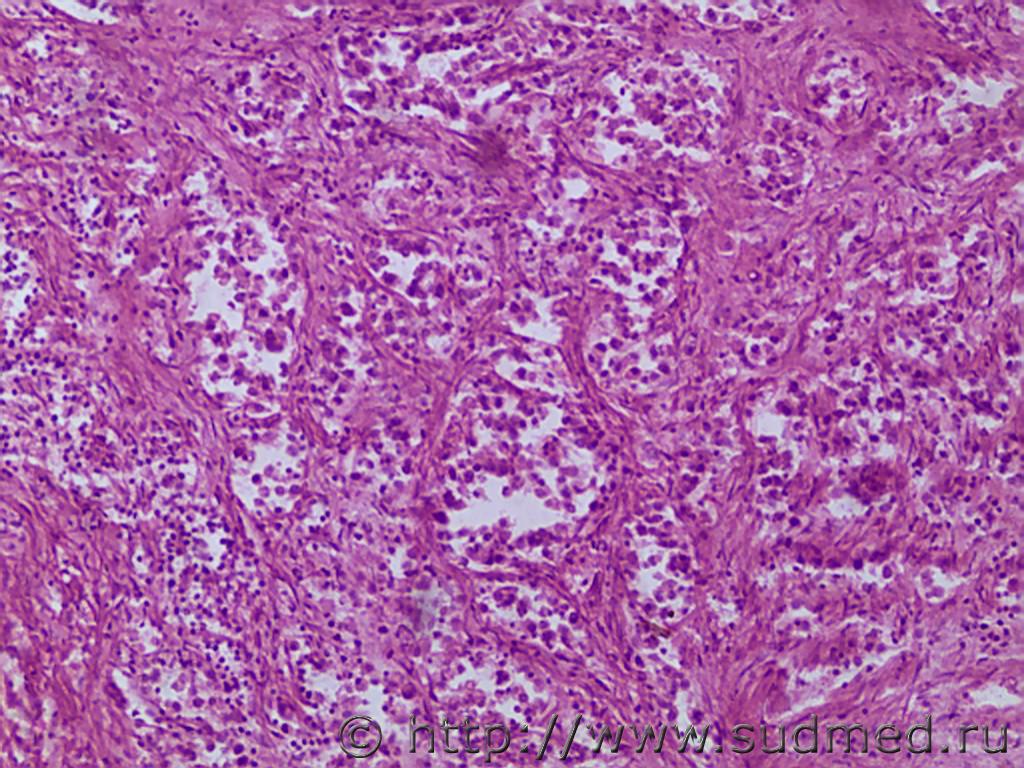

Уважаемые коллеги, не могу определиться с типом опухоли тонкой кишки. На вскрытии эксперт находит хроническую язву 12-типерстной кишки с обострением, аррозией сосуда; в желудке 1,5 литра крови. Покойница 1946г.р, ВИЧ 3 степени. В микропрепаратах похоже на стромальную опухоль, кое-где клетки похожие на перстни.

Перстневидноклеточный рак (8490/3).

ГИСТ растёт не из слизистой оболочки и не изъязвляется.

В Вашем случае макроскопически имеет место язва-рак,вероятнее всего,луковицы двенадцатиперстной кишки.Что это микро - написал выше.Перстневидноклеточный рак - это одна из форм низкодифференцированной аденокарциномы.Вы же видите железистые (ацинарные) структуры ?

Не остались ли слизистая, на фото мышечный слой с инфильтрацией. Нашел тоже в 1-м фото в правом нижнем углу классическую одну перстневидную клетку и единичные по середине перевернутые и часть с эксцентрично расположенные пока округлые ядра видимо еще низкодифференцированные.